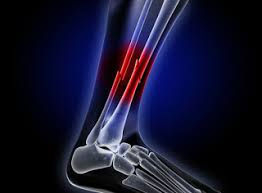

Fraturas complexas

Hoje em dia, as fraturas deslocadas ou complexas são difíceis de tratar. Muitas das vezes exigem cirurgias e isso demora em um longo tempo de recuperação do paciente.

E o doente normalmente precisa permanecer com a parte do corpo que foi quebrada imobilizada até que a cicatrização completa ocorra.

Assim, a nova técnica com irradiação de plasma, além de promissora, pode auxiliar em uma volta dos movimentos mais precocemente.